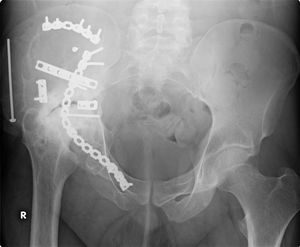

طب العظام يعنى بشكل عام بتصحيح الكسور جراحيا وتجبيرها إضافة إلى عمليات إصلاح وتبديل المفاصل التالفة. بالإضافة إلى أنواع أخرى من العمليات الجراحية التي تعالج أمراض العظام والجهاز الحركي.

جراحة العظام فرع من فروع الطب يعالج اعتلالات العظام والعضلات والأنسجة المتصلة بها. ويُدعى الأطباء الذين يُمارسون جراحة العظام جراحو العظام. وهم يُعالجون مُشكلات طبية كثيرة في هذا المجال منها الكسور، وإصابات الأوتار والأربطة، وتشوهات الأطراف والعمود الفقري. وقد توجد بعض الاعتلالات العظمية منذ الولادة، بينما تظهر اعتلالات أخرى أثناء الطفولة بسبب مشكلات تتعلق بالنمو، أو في فترة متأخرة من العمر نتيجة للشيخوخة. كما تحدث اعتلالات أخرى نتيجة إصابة ما أو مرض. ويُشكل المصابون في حوادث السيارات، أو الأنشطة الرياضية أو أثناء التنزه والاستجمام عددًا كبيرًا من المرضى الذين يعالجهم اختصاصيو العظام. ويصف الأطباء لمعالجة الاعتلالات العظمية الأدوية، والجراحة، والعلاج الطبيعي. وقد يقوم الاختصاصي، على سبيل المثال، بإجراء جراحة لتقويم كسر أو تشوه. وبعد الجراحة قد يستخدم الاختصاصي قالبًا أو مقبضًا، ويصف العلاج الطبيعي كي يساعد على الشفاء. مثل هذه المعالجة قد تشمل استخدام جهاز يطلق نبضات كهربائية تُساعد العظم على الالتئام. كما قد يقوم الاختصاصي بإجراء جراحة لاستبدال مفصل من البلاستيك أو المعدن أو من مواد أخرى بمفصل ملتهب، أو مصاب. والمفصل الذي يستبدل عادة أكثر من غيره، هو مفصل الورك.

- كسور العظام (Fractures)

- عمليات كسور عنق عظمة الفخذ.

- عمليات كسور ما بين مدوري عظمة الفخذ.